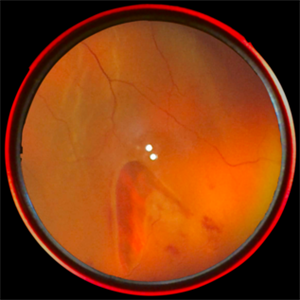

Subhyaloid Hemorrhage

Jan 26 2020 by Prithvi Chandrakanth

27-year-old male presented with sudden diminution of vision with visual acuity of 2/60 in the right eye. visual acuity of the left eye was 6/6, fundus examination revealed subhyaloid hemorrhage in the right eye and normal fundus in the left eye.

Photographer: Dr.PRITHVI CHANDRAKANTH, ARAVIND EYE HOSPITAL, UDUMALPET

Imaging device: TRASH TO TREASURE RETCAM

Condition/keywords: retcam, smartphone fundus photography, subhyaloid hemorrhage